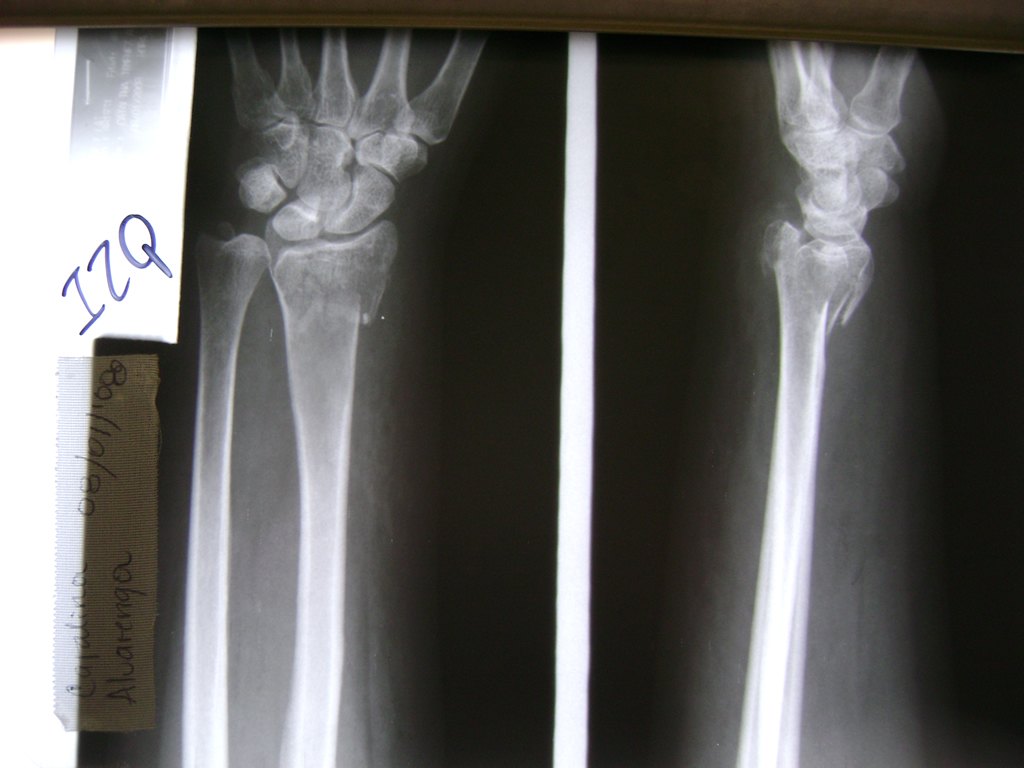

Calcaneo - Cirugías de Muñecas y Manos

Los procedimientos más comunes en cirugía de la mano son aquellos destinados a reparar traumatismos, incluyendo lesiones de tendones, nervios, vasos sanguíneos, y articulaciones; huesos fracturados; y quemaduras, cortes, y otros daños de la piel.